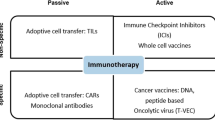

Recent immunotherapeutic approaches have evolved as powerful treatment options with high anti-tumour responses involving the patient’s own immune system. Passive immunotherapy applies agents that enhance existing anti-tumour responses, such as antibodies against immune checkpoints. Active immunotherapy uses agents that direct the immune system to attack tumour cells by targeting tumour antigens. Active cellular-based therapies are on the rise, most notably chimeric antigen receptor T cell therapy, which redirects patient-derived T cells against tumour antigens. Approved treatments are available for a variety of solid malignancies including melanoma, lung cancer and haematologic diseases. These novel immune-related therapeutic approaches can be accompanied by new patterns of response and progression and immune-related side-effects that challenge established imaging-based response assessment criteria, such as Response Evaluation Criteria in Solid tumours (RECIST) 1.1. Hence, new criteria have been developed. Beyond morphological information of computed tomography (CT) and magnetic resonance imaging, positron emission tomography (PET) emerges as a comprehensive imaging modality by assessing (patho-)physiological processes such as glucose metabolism, which enables more comprehensive response assessment in oncological patients. We review the current concepts of response assessment to immunotherapy with particular emphasis on hybrid imaging with 18F-FDG-PET/CT and aims at describing future trends of immunotherapy and additional aspects of molecular imaging within the field of immunotherapy.

Recent immunotherapeutic approaches have emerged as powerful treatment options with high anti-tumour responses. These effects can be achieved by redirecting, stimulating, or genetically reprogramming the patient’s own immune system to target cancer cells. Passive immunotherapy is the most frequent form of immunotherapy, involving agents that enhance existing anti-tumour responses, such as antibodies against immune checkpoints such as cytotoxic T-lymphocyte-associated protein 4 (CTLA-4), programmed cell death protein (1 PD-1), and programmed death-ligand 1 (PD-L1). Active immunotherapy uses agents that direct the immune system to attack tumour cells by targeting tumour antigens (e.g., vaccines such as Bacillus Calmette–Guérin in bladder cancer). Active cellular-based therapies are on the rise, most notably chimeric antigen receptor (CAR) T cell therapy, which redirects patient-derived T cells against tumour antigens [1,2,3].

Immunotherapy: the state of the art

The idea of utilising immune cells to eradicate malignant disease dates back to 1970, when Buckner et al. [8] reported the first successful allogeneic bone marrow transplantation in a patient suffering from leukaemia. This technique grew to become an indispensable means of treatment for many forms of haematologic malignancies. In contrast, recent immunotherapeutic approaches aim to achieve anti-tumour responses by redirecting, stimulating, or genetically reprogramming the patient’s own immune system to target cancer cells. These strategies include antibody-based treatments, immune checkpoint inhibitors, and chimeric antigen receptor (CAR)-T cells as most prominent examples.